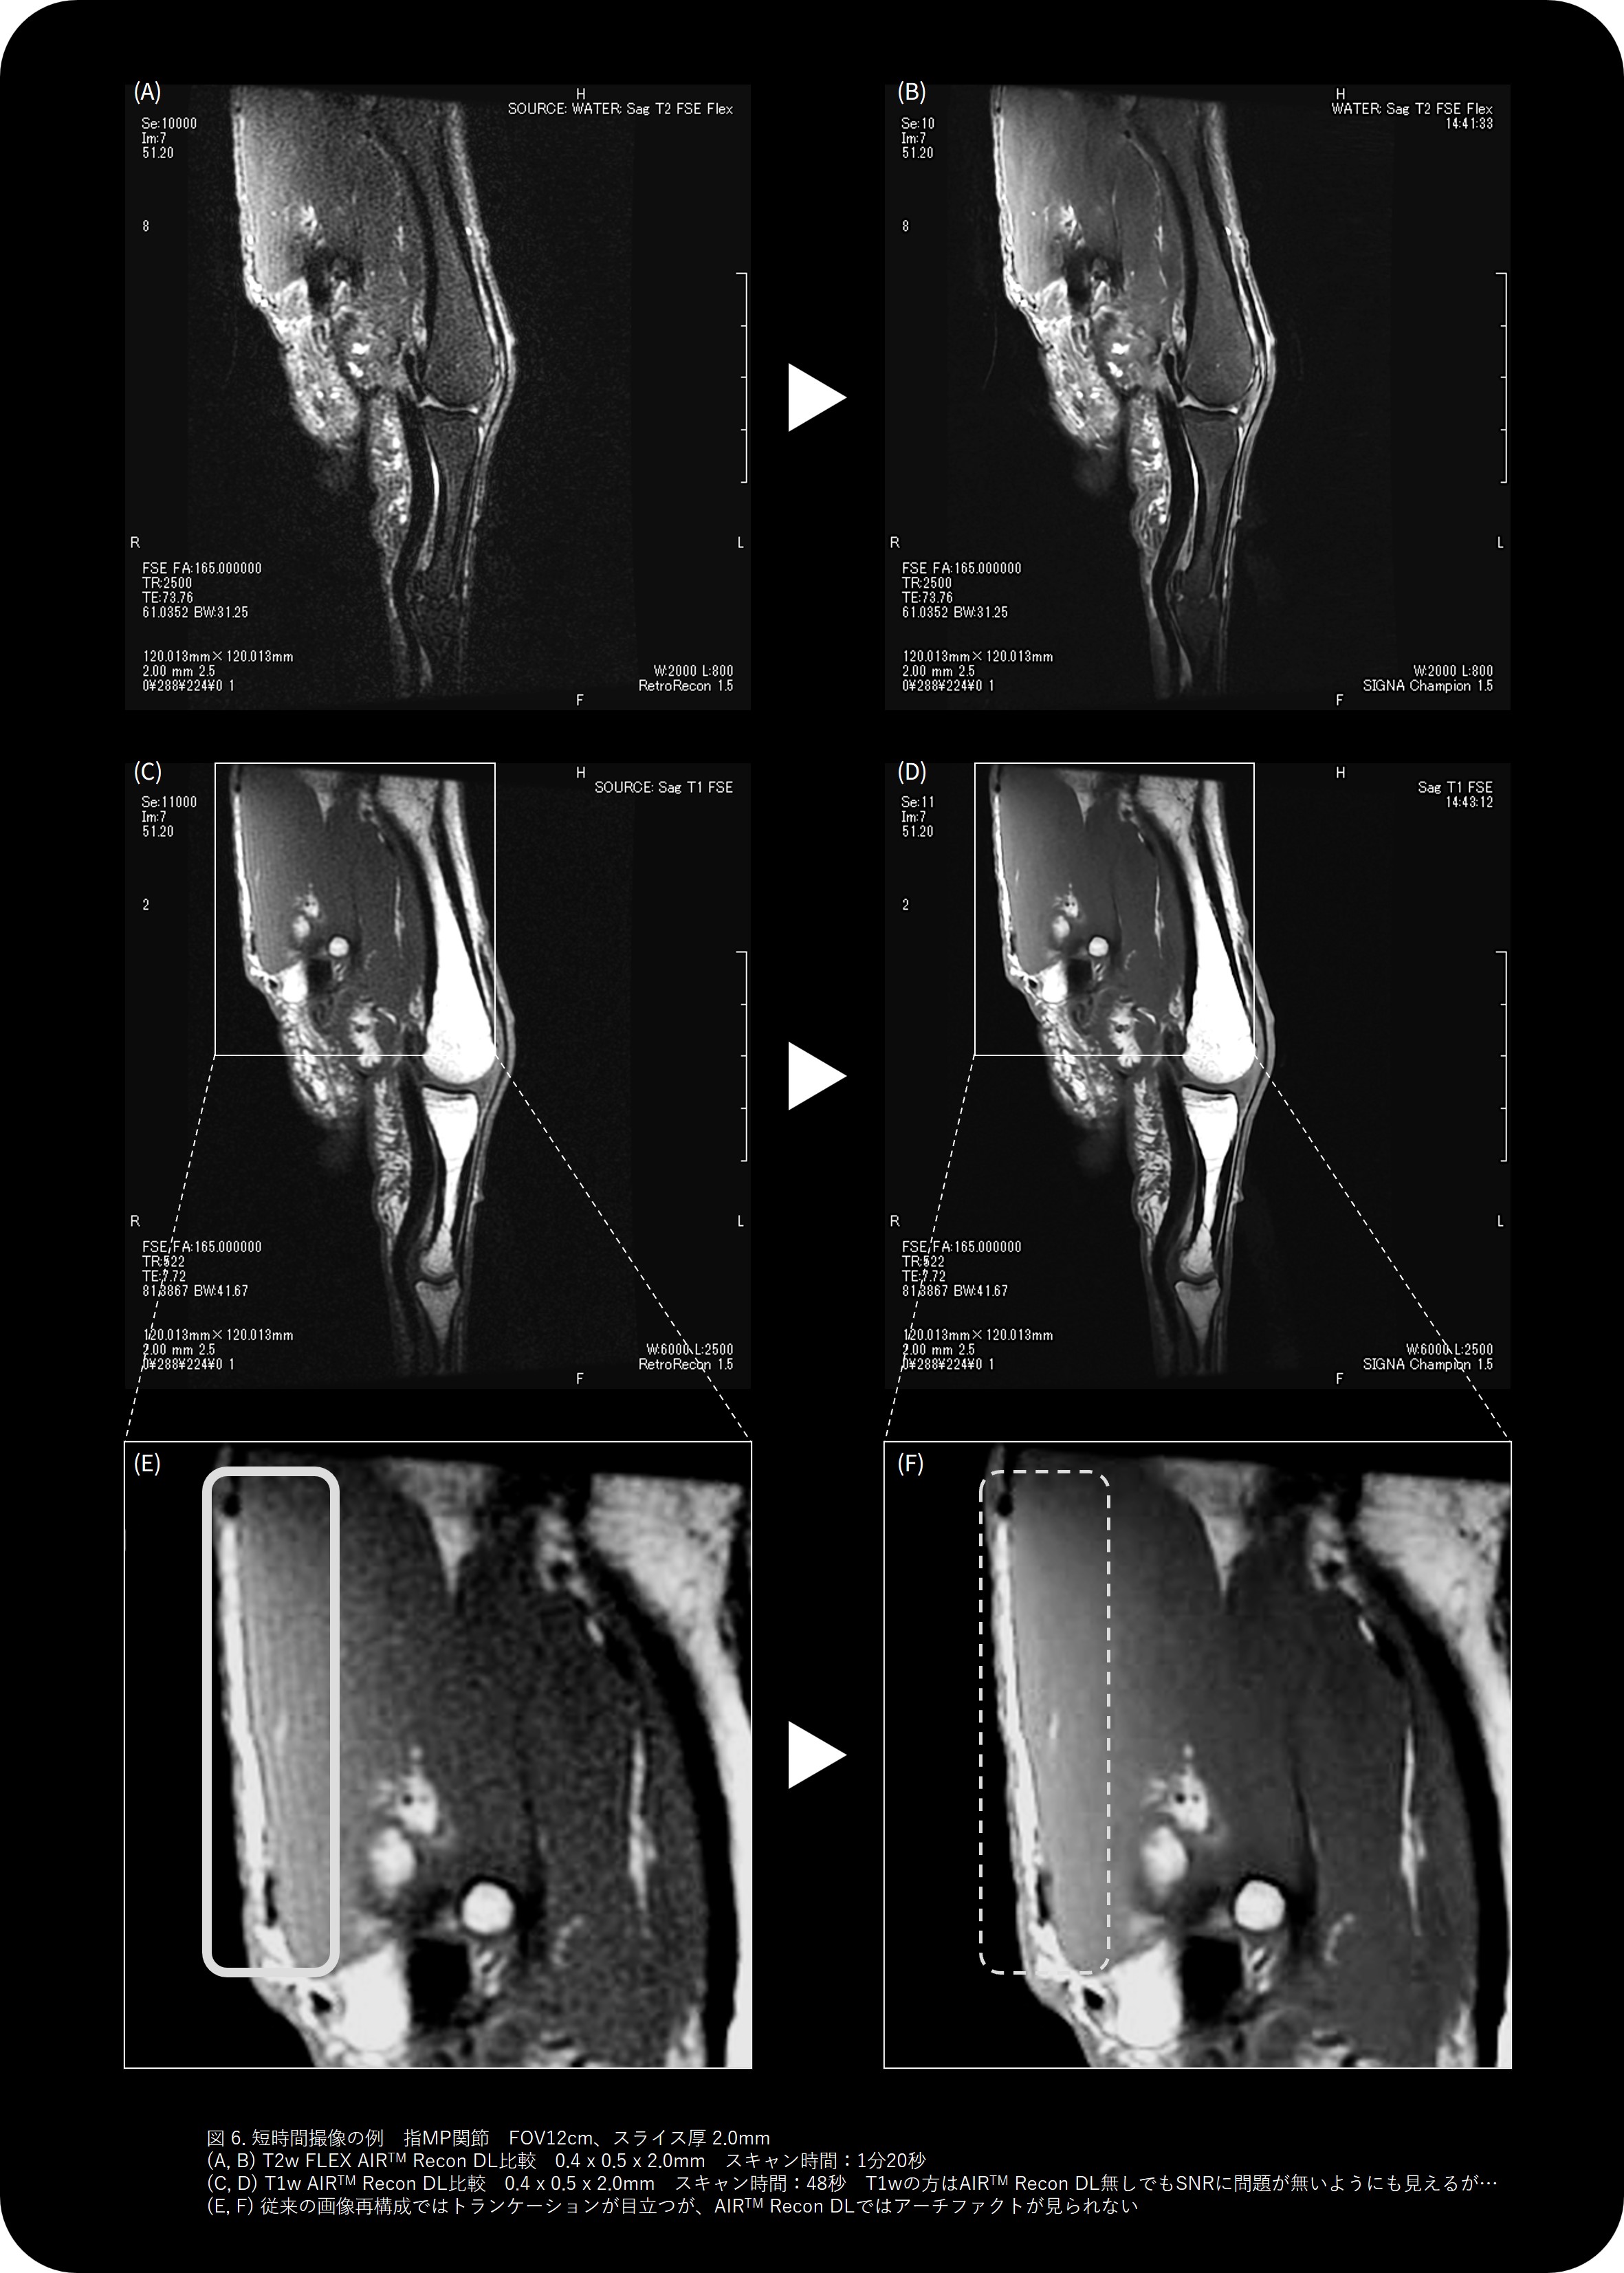

導入後、最も印象的だったのは、短時間でも高画質が維持される点です。 (図5-7)

34秒のSagittal T2w撮像では、従来法に比べ動きに強く、ルーチン撮像を置き換えることができました。この画像を見て「ルーチンを変えよう!」と即決しました。現在ではFast scanを34秒、通常スキャンも50秒台に変更しています。

従来20年間使い続けてきたgapless DWIのルーチンが(前装置ではSNR等の観点から諦めていましたが) 最新技術によって再評価され、新たな形で “復活” もしました。さらに厚みの設定によるSNR変化への理解も深まりました。3.0mmでは明瞭に見える信号が、5.0mmにするとボケてしまうケースもあり、厚みを細かく調整することで診断能を最大化できることを実感しています。 AIR™ Recon DLでは、高SNRと高分解能を両立できるため、1分半の短時間撮像でも高画質が維持される点が特に印象的です。

使い勝手の面でも、設定項目が「Low」「Medium」「High」の3段階のみで、他社DLRのような複雑なパラメータ操作が不要です。どの技師が撮像しても安定した品質が得られるため、施設間の画質差も少なく、地方中規模病院でも “均一なクオリティ” を提供できる安心感があります。

さらに、T2 FLEXやT1強調画像をAIR™ Recon DLで撮像し、指関節などの微細構造を1分半程度で描出できるようになりました。以前は10分以上かかっていた検査が短縮され患者負担の軽減とスループット向上の両立を実現しています。